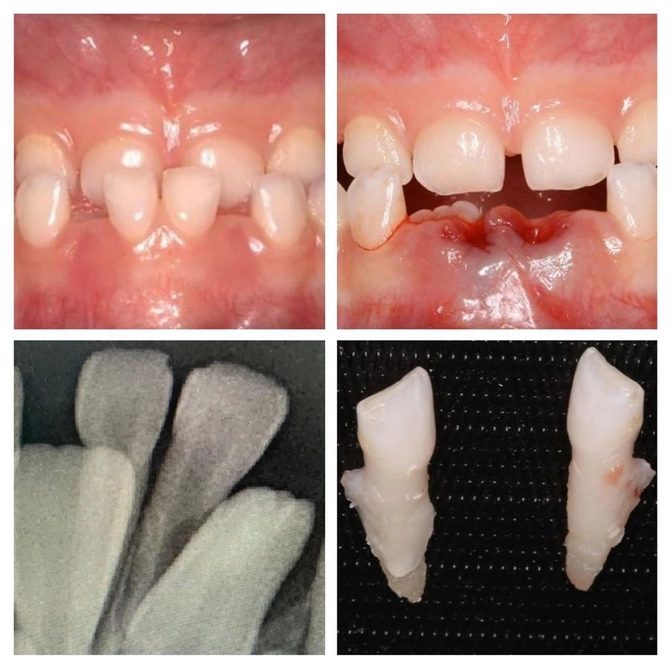

Зубки-долгожители никак не хотели уступать место новым "жильцам".

Нижние молочные резцы так крепко сидели и не хотели выпадать, что пришлось принудительно им помочь.

Удалила 2 молочных зуба (нет, ЗУБИЩА) под местной анестезией (укол)

Девочке 6 лет.

Резцам пора меняться.

Но корни нижних были длинные, а постоянные зубки уже начали прорезываться за ними.

Должно быть понятно (ну хотя бы примерно) по снимку - он тоже на фото.

Показания к удалению ортодонтические, у девочки мезиальный прикус.

Это вид неправильного прикуса, при котором нижняя челюсть выдвинута вперед относительно верхней.

Видите на фото, как нижние резцы перекрывают верхние?

Это не норма!